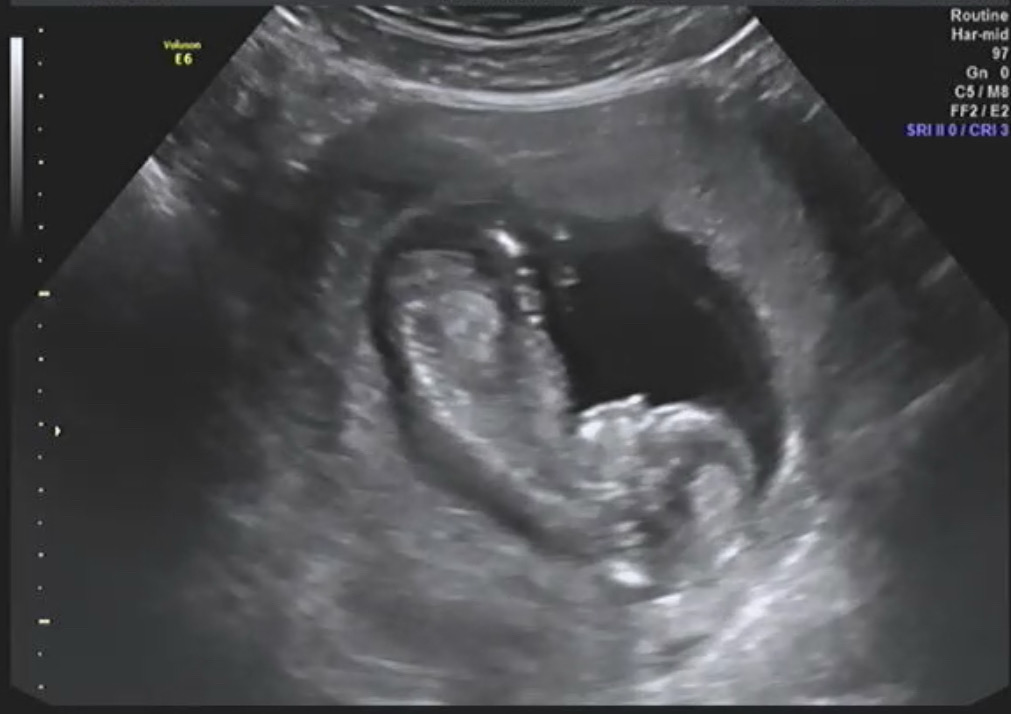

12주5일차 각도법좀 봐주세요ㅠㅠ

처음이라 아무것도 모르겟어요ㅠㅠ